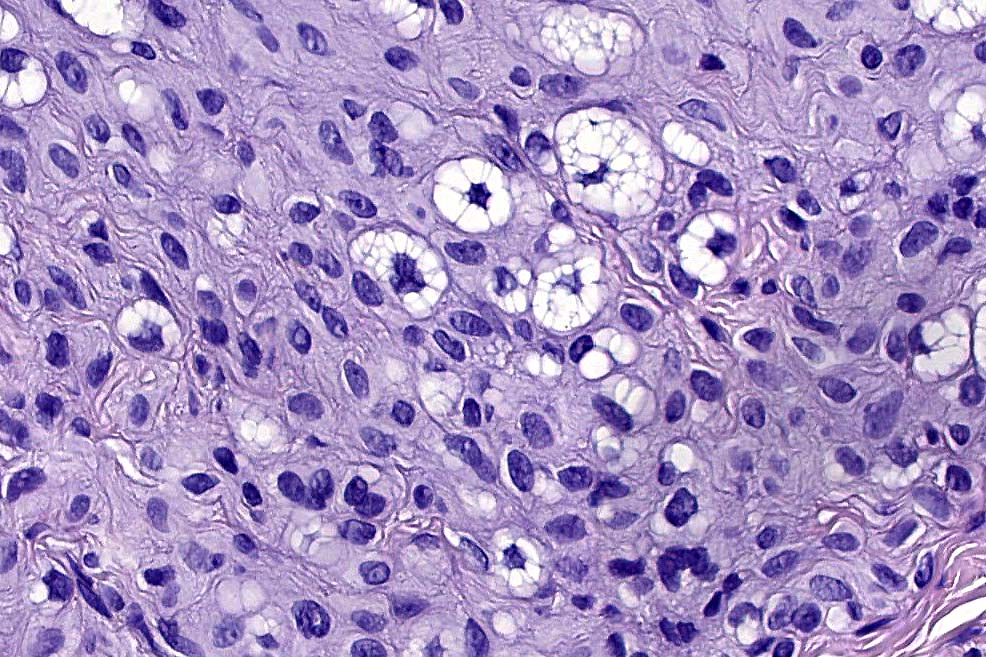

.Balloon cell change is most often seen in banal melanocytic nevi but it has also rarely been described in cellular blue nevus, dysplastic nevus, combined nevus, halo nevus & Spitz nevus. Lesions with <50% of balloon cells are sometimes described as nevi with balloon cells. Nevi with >50% balloon cells are described as balloon cell nevus.

.Balloon cell nevs genrally has uniform, hyperchromatic nuceli (as opposed to the vesicular nuclei with prominent nucleoli) seen in melanoma. Mitoses are absent.(In my experience, balloon cell melanoma is more common than balloon cell nevus).

. In some balloon cell nevi, the microvesicles may result in nuclear scalloping reminiscent of a sebaceous tumor. In cases where there is real doubt, immunohistochemistry (S100), SOX10) will resolve the problem.